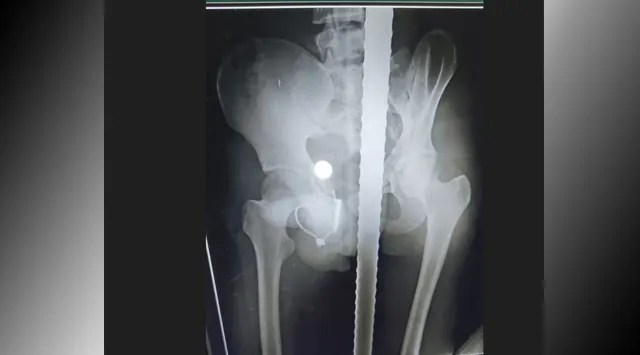

ବାଲିଗୁଡା : ଦୀର୍ଘ ଚାରିଘଣ୍ଟାର ଅପରେସନ୍ ପରେ ଯୁବକଙ୍କ ମଳଦ୍ୱାରରେ ପଶିଥିବା ଶାବଳକୁ ବାହାର କରାଯାଇଛି। ବ୍ରହ୍ମପୁର ଏମ୍କେସିଜି ମେଡିକାଲର ସର୍ଜରୀ ବିଭାଗ ବରିଷ୍ଠ ଡାକ୍ତରମାନଙ୍କ ଦ୍ଵାରା ଅସ୍ତ୍ରୋପଚାର ସଫଳ ହୋଇଛି। ୧୬ ବର୍ଷୀୟ ଶକ୍ତି ପାଟଗୁରୁଙ୍କ ମଳଦ୍ୱାରରୁ ବାହାର କରାଯାଇଛି ଶାବଳ । ଅସ୍ତ୍ରୋପଚାର ପରେ ଶକ୍ତି ସୁସ୍ଥ ଅଛନ୍ତି। ତାଙ୍କୁ ବର୍ତ୍ତମାନ ଆଇସିୟୁରେ ରଖାଯାଇଛି। ଦୁଇ ଦିନ ଯାଏ ଆଇସିୟୁରେ ରଖି ତାଙ୍କ ସ୍ୱାସ୍ଥ୍ୟବସ୍ଥା ଯାଞ୍ଚ କରାଯିବ । ତାଙ୍କୁ ଘରକୁ ଯିବା ପାଇଁ ଅନୁମତି ଦିଆଯିବ। ମଳଦ୍ୱାର ଦେଇ ଶାବଳ ପଶିବା ଯୋଗୁ ଶରୀରର ବିଭିନ୍ନ ସ୍ଥାନରେ ଆଘାତ ଲାଗିଛି। ଶକ୍ତିଙ୍କ ସ୍ୱାସ୍ଥ୍ୟବସ୍ଥାରେ ସାମାନ୍ୟ ସୁଧାର ଆସିବା ପରେ ତାଙ୍କର ଅଧିକ ଚିକିତ୍ସା କରାଯିବ। ସର୍ଜରୀ ବିଭାଗର ଆସୋସିଏଟ ପ୍ରଫେସର ଆଇ.ଗୋପାଲ ଏହି ସୂଚନା ଦେଇଛନ୍ତି ।

ଗତକାଲି ମଳଦ୍ୱାରରେ ଶାବଳ ପଶିଯିବାରୁ ଯୁବକ ଗୁରୁତର ହୋଇଥିଲେ। କନ୍ଧମାଳ ଜିଲ୍ଲା କୋଟଗଡ ଥାନା ତଳ ସୁବର୍ଣ୍ଣଗିରି ଗାଁର ଘଟଣା। ଗୁରୁତର ଯୁବକଙ୍କୁ ପ୍ରଥମେ କୋଟଗଡ଼ ,ପରେ ବାଲିଗୁଡା ମେଡିକାଲକୁ ସ୍ଥାନାନ୍ତର କରାଯାଇଥିଲା । ପରେ ସ୍ଥିତି ଗମ୍ଭୀର ହେବାରୁ ତାଙ୍କୁ ବ୍ରହ୍ମପୁର ବଡ ମେଡିକାଲକୁ ସ୍ଥାନାନ୍ତର କରାଯାଇଥିଲା। ତଳ ସୁବର୍ଣ୍ଣଗିରି ସରକାରୀ ସ୍କୁଲ ରିପ୍ୟାରିଙ୍ଗ୍ କାର୍ଯ୍ୟ କରୁଥିବା ସମୟରେ ଏଭଳି ଅଘଟଣ ଘଟିଥିଲା। ପ୍ରଥମେ ଆଜବେଷ୍ଟସ ଭାଙ୍ଗି ଶାବଳଟି ତଳେ ଖସି ପଡିଥିଲା। ଶାବଳଟି ଉପରକୁ ମୁନିଆ ପଟେ ରହିଥିଲା l ପରେ ଶକ୍ତି ବି ଆଜବେଷ୍ଟସ ଉପରୁ ତଳକୁ ଖସି ପଡ଼ିଥିଲେ । ଭୂଇଁରେ ଉପର ମୁହାଁ ହୋଇ ରହିଥିବା ଶାବଳଟି ଶକ୍ତିଙ୍କ ମଳଦ୍ୱାରରେ ପଶି ଯାଇଥିଲା ।